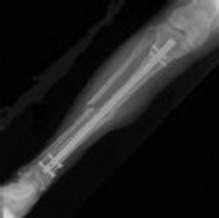

Figure 1 is the radiograph taken 6 weeks ago of a 41-year-old woman with persistent pain in her right leg after sustaining a tibia fracture 12 months ago in a motor vehicle collision. On examination, she has well-healed scars and a well-healed flap on the medial aspect at the level of the fracture. She reports having an infection after the initial surgery, which resulted in debridement of the soft tissue and need for the local rotational flap. There are no changes at the fracture site as shown in the most recent radiograph (Figure 2). She is healthy and has no comorbidities.

What is the best next step in the patient’s evaluation?

---

Based on the radiographs shown in Figures 1 and 2, her tibia is a

Assuming her workup is negative for any other causes, what is the best treatment option?